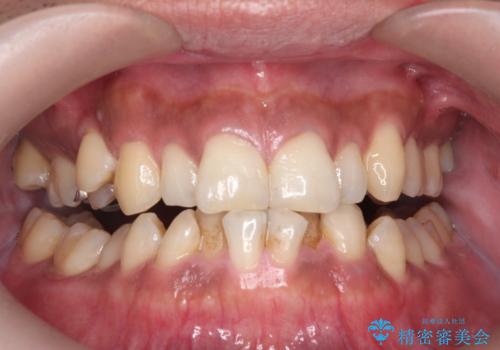

コーヒー、タバコなどで着色した歯をPMTCで、きれいに!!

- 長年の喫煙とコーヒーによる歯の、着色をとりたいと来院されました。

かなり汚れがこびりついていたので、PMTC(歯科医院で行うプロフェッショナルクリーニング)60分コースを

おすすめしました。

歯の着色だけでなく、汚れもとれ歯の表面がツルツルなって気持ちがいいと

大変満足していただけました。